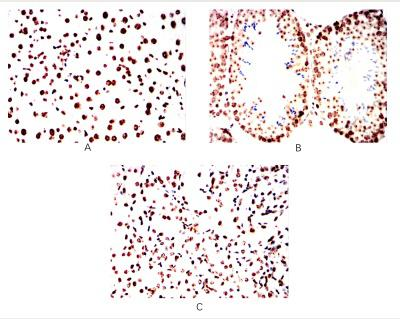

在黑色素瘤研究体系中,人源P16抗体的应用覆盖多个关键环节。在分子机制研究层面,借助该抗体的特异性结合能力,可精准定位P16蛋白在黑色素瘤细胞中的表达位置与分布情况,为解析P16蛋白在黑色素瘤发生发展中的作用机制提供直观依据。在诊断研究领域,基于人源P16抗体的高特异性与高灵敏度,可开发相关检测试剂,用于黑色素瘤的早期筛查与诊断,助力提升黑色素瘤早期检出率。此外,在治疗研究方面,人源P16抗体还可作为靶向载体,搭载治疗药物或显像剂,为黑色素瘤靶向治疗研究与疗效监测提供技术支撑。